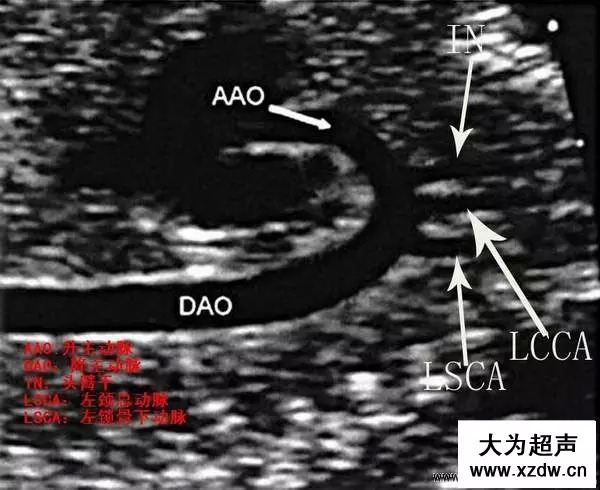

產(chǎn)科超聲正常圖片